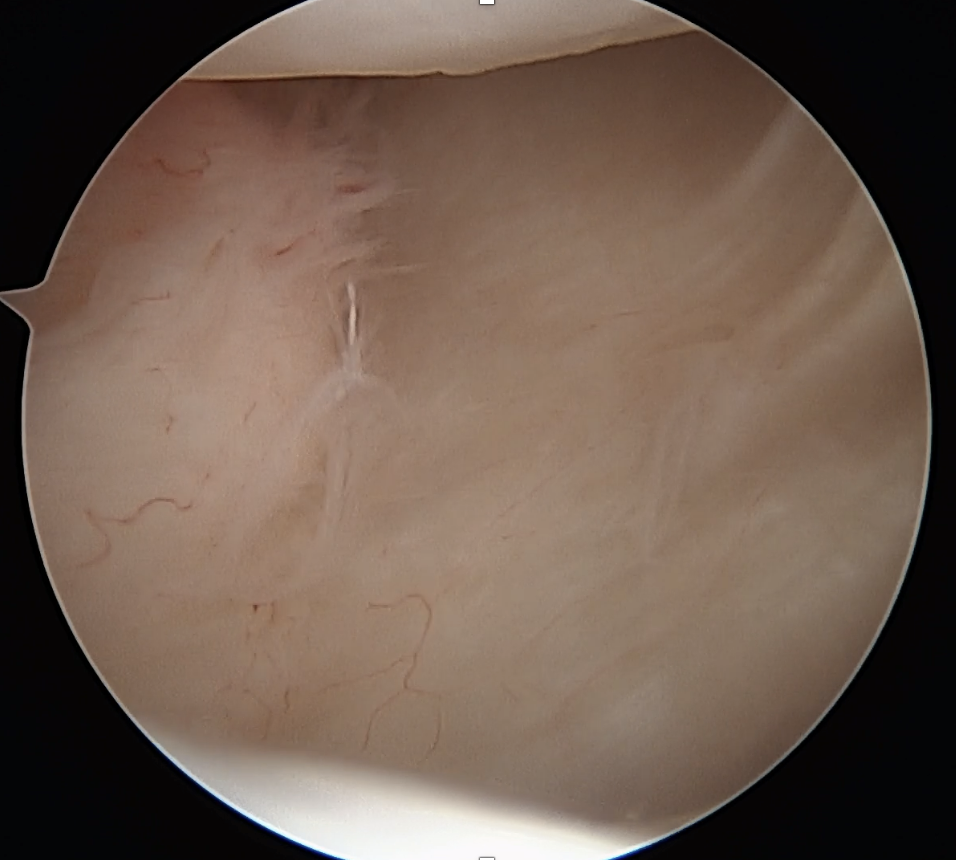

Arthroscopy

Capsule tear anteriorly, extending up into humeral insertion